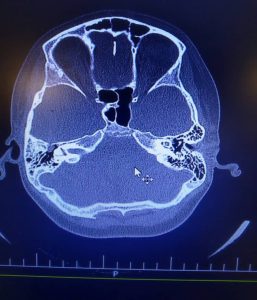

Langerhans cell histiocytosis (LCH) is a very rare condition that commonly affects the head and neck region. There are very few cases of isolated laryngeal involvement by LCH, mostly reported in pediatric patients. Here, we report a case of laryngeal LCH in a 62-year-old woman presenting with a neck mass several weeks ago. The clinical and histopathological findings are reported with a brief discussion about the disease.